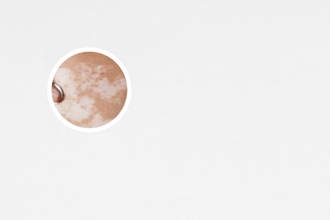

白斑的早期癥狀圖

白斑的早期癥狀較顯然的特征就是皮膚顏色的改變。在白斑部位,皮膚的色素會逐漸消失,形成白色或乳糜色斑塊。初期白斑一般較小,局部色素消失程度也相對較輕。

隨著白斑的形成,皮膚上會出現(xiàn)不均勻的顏色變化。白斑通常會呈現(xiàn)為白色或乳白色的斑塊,邊緣有時會出現(xiàn)清晰界限,有時則比較模糊。特別是在暴露于陽光下時,白斑的顏色差異可能更加顯然。